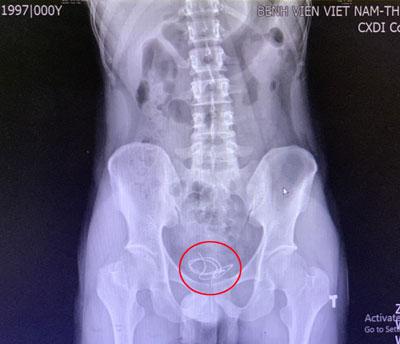

Các bác sĩ Khoa Ngoại thận tiết niệu, Bệnh viện Việt Nam - Thụy Điển Uông Bí (Quảng Ninh) vừa tiến hành can thiệp lấy ra đoạn dây tai nghe điện thoại dài 20cm trong bàng quang của một nam thanh niên.

Theo đó, bệnh nhân 25 tuổi nhập viện với triệu chứng tiểu khó, tiểu buốt, tiểu rắt. Qua thăm khám, dựa trên phim chụp X-quang, các bác sĩ phát hiện một đoạn dây tai nghe dài chừng 20cm trong bàng quang của nam thanh niên. Người bệnh thừa nhận chính anh đã tự nhét dị vật vào niệu đạo (ống dài nối từ bàng quang ra lỗ tiểu để đưa nước tiểu ra bên ngoài, niệu đạo còn có chức năng trong việc dẫn tinh dịch ra ngoài). Không may đoạn dây tai nghe bị đẩy vào quá sâu, dẫn đến mắc kẹt.

Các bác sĩ đã tiến hành nội soi bàng quang để lấy dị vật ra ngoài cho bệnh nhân. Theo Ths.Bs Nguyễn Như Trung - Khoa Ngoại thận tiết niệu Bệnh viện, dị vật là 1 đoạn dây tai nghe điện thoại nằm cuộn tại bàng quang của người bệnh. Tiến hành lấy bỏ dị vật ra ngoài nhận thấy niêm mạc bàng quang, niệu đạo đã có hiện tượng viêm đỏ.